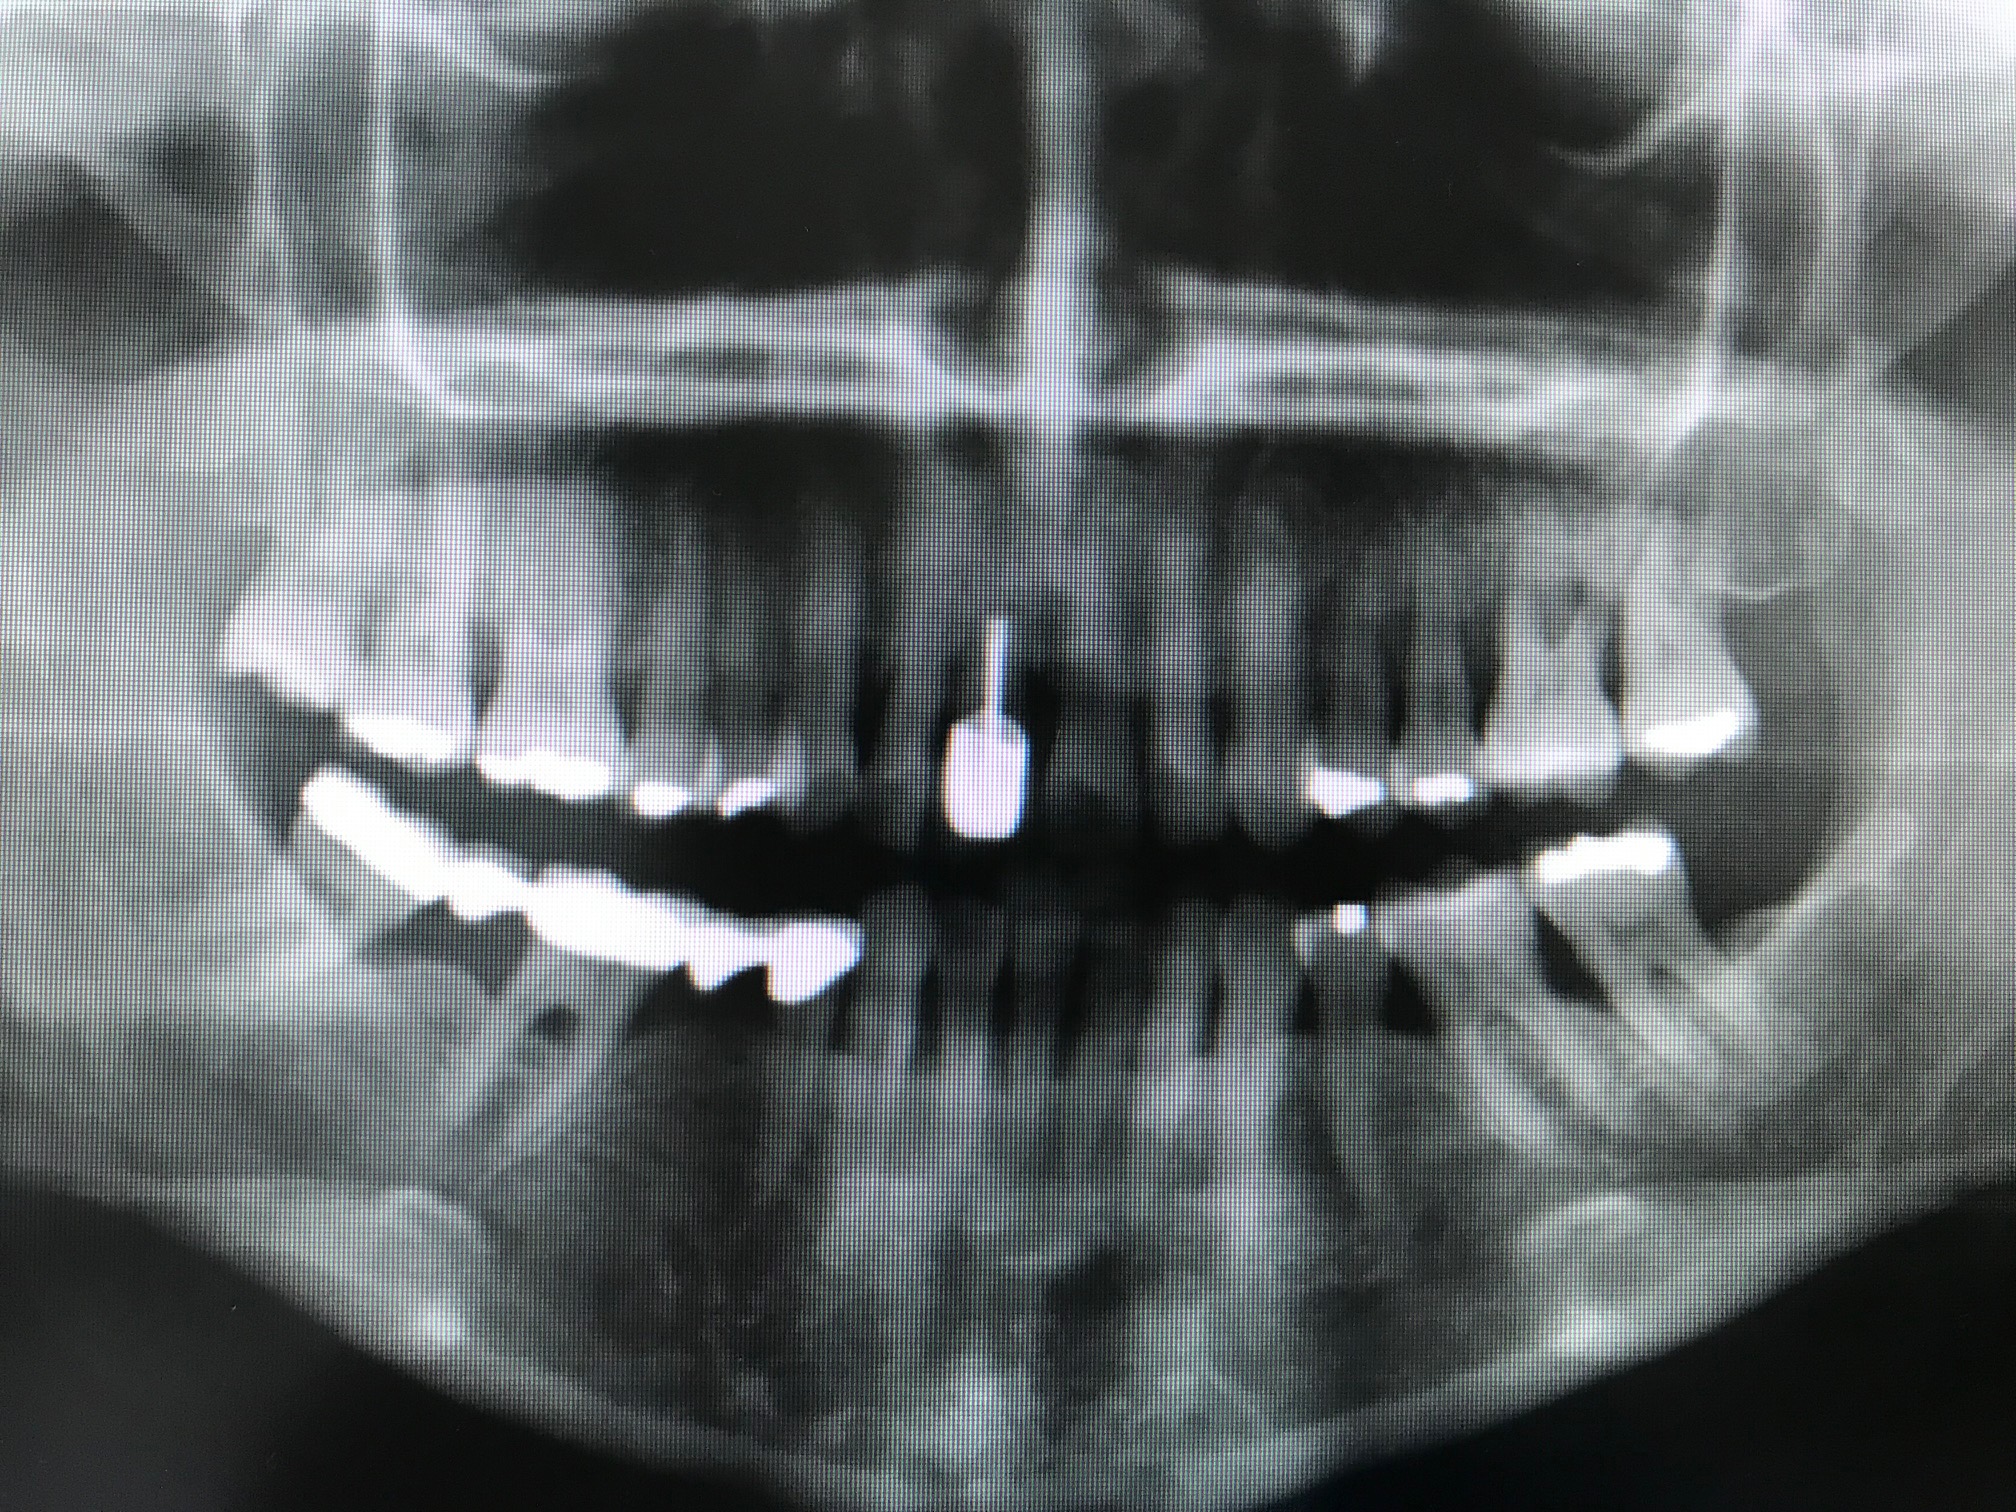

Bildbeschreibung:

Erstaufnahme. Patientin kommt wegen beweglicher Zähne oben links (rechte Seite). Trotz Parodontalbehandlung keine Festigkeit - es fehlt zu viel Knochen. Patientin ist starke Raucherin. Nach Gespräch hat Sie ihren Konsum an Zigaretten minimiert.

Bildbeschreibung von li. nach re.

2 Monate Extrusionstherapie der 3 Zähne, danach folgt die Extraktion, abtrennen von Wurzelscheiben je Zahn am letzten Zahn die volle Wurzelspitze wegen der Kieferbreite. Das vitale Bindegewebe auf den Wurzelsegmenten gibt offensichtlich biologische Informationen an den umgebenden Knochen auch in der Tiefe, weiter zu wachsen. Z.Zt. wird weltweit an diesem Phänomen geforscht.

Zustand nach 4 Monaten : der Knochen ist fast gesamt nachgekommen.

Es konnten wie geplant 3 Implantate einoperiert werden, in guter Position, umgeben von ausreichendem Knochen, es musste nichts nachaugmentiert werden, auch wenn die Atrophie durch das jahrelange Rauchen besonders im Gaumenbereich erheblich ist.

3 Implantate in geplanter Position umgeben von eigenem Knochen.

Diese werden bereits nach 3 - 4 Monaten mit Einzel Kronen versorgt.